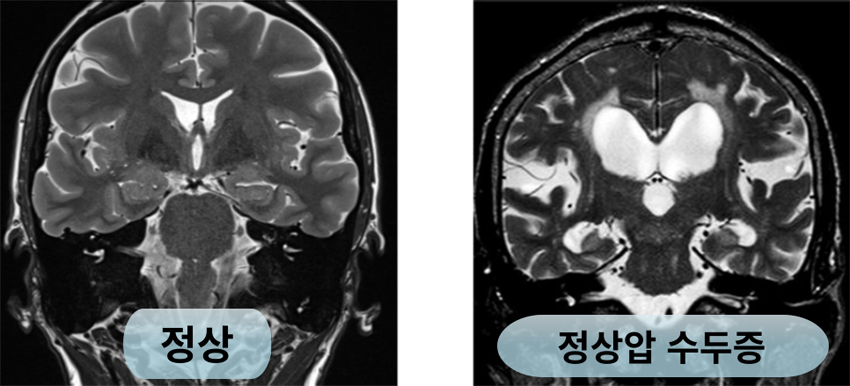

뇌와 척수 안에는 뇌척수액이라는 액체가 순환하는데, 이 뇌척수액의 양이 많아진 것이 수두증입니다. 뇌척수액이 증가하고, 뇌실이 넓어졌는데도 뇌압이 정상인 경우를 따로 정상압 수두증이라고 합니다. 정상압 수두증은 뇌수막염, 두부 외상, 출혈 후에 이차성으로 발생할 수 있으며, 특별한 선행질환이 없이 일차성(특발성)으로 발생하기도 합니다. 노인 인구의 100명중 2명에서 발생하는 비교적 흔한 질환으로, 알츠하이머병이나 파킨슨병으로 오인되는 경우도 있습니다.

제일먼저 앞서 설명한 특징적인 세 가지 증상으로 정상압 수두증을 의심하게 됩니다. 영상학적으로는 뇌 CT로 뇌실의 크기와 뇌실주변 저음영을 관찰하게 되고, 뇌 MRI로는 동반되어있는 두개강내 병변 감별 및 뇌위축 정도를 평가할 수 있습니다. 정상압수두증의 증상은 흔히 치매의 원인 중 가장 잘 알려진 알츠하이머병, 파킨슨병 등과 비슷하게 나타나는 경우가 많아 감별진단이 필요합니다. 정확한 진단을 위해 추가로 특수 MRI 및 PET 등의 검사를 통해 감별에 도움을 얻을 수 있으며, 증상의 정도에 대한 정확한 정량적 평가를 위해 신경인지검사나 보행관련 검사들을 시행합니다. 또한 정상압 수두증이 진단되면 요추천자를 통한 뇌척수액 배액 검사를 통해 수술 유효성을 평가합니다.